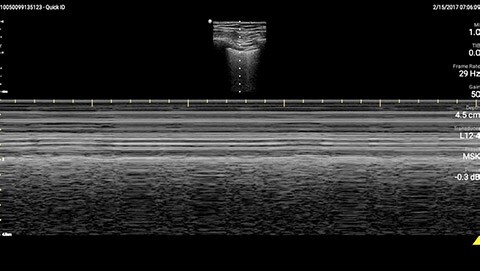

In this Lumify case study and summary video, Dr. Sara Nikravan discusses how she used her Philips Lumify handheld ultrasound system to guide the diagnosis and treatment of a patient experiencing shortness of breath.

Determining the cause of respiratory distress in the acutely ill can be challenging. POCUS with a three-point exam (F-TTE, IVC collapsibility, and lung ultrasound), as performed above, has been endorsed in this patient population as it can increase diagnostic accuracy in a timely fashion, especially as it pertains to acute decompensated heart failure.4 Furthermore, the use of a small portable device allows for convenience with rapid setup and use while minimizing the uptake of space. This becomes especially important when caring for patients that often have many providers attempting to provide care and initiate interventions at the same time, given the acute nature of their illness and potential for further rapid de-compensation.